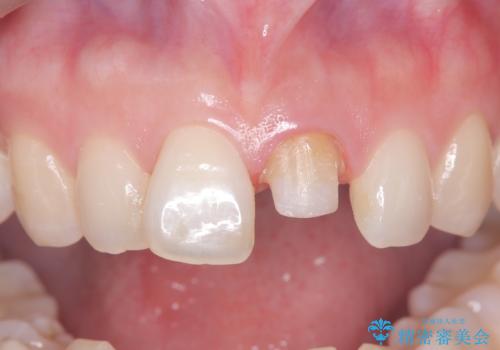

前歯の変色を改善し、本来の自然な美しさへ

- 以前の根管治療後に生じた左上1番の前歯の変色を気にされて来院されました。患者様のご希望を伺い、オールセラミッククラウンによる審美修復を提案。既根管治療歯であるため、土台の状態や周囲の歯の色調を詳細に分析し、患者様の顔貌に調和した自然で美しい口元を実現するための治療計画を立てました。

治療では、変色した歯を形成した後、精密なシリコン印象材で型取りを行いました。この型取りから、患者様の歯の色や形、透明感を忠実に再現したオーダーメイドのオールセラミッククラウンを作製。金属を一切使わないため、アレルギーの心配がなく、歯ぐきの変色も防ぎます。技工士と連携し、天然歯と見分けがつかないほどの自然な仕上がりを追求。機能性と審美性を兼ね備えた、理想的な前歯を取り戻していただけました。